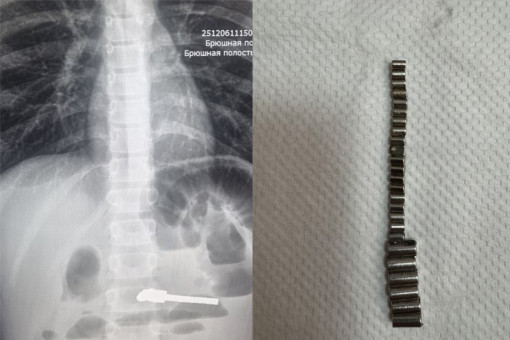

Ежегодно пациентами хирургического отделения ДГКБ № 1 становятся несколько детей, из ЖКТ которых врачи извлекают инородные тела.

25 инородных тел достали из мальчика в Новосибирске